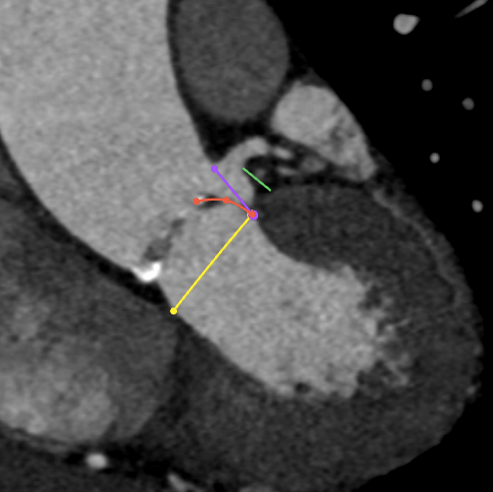

Annulus

长径: 24.8 mm

周长: 68.6 mm

面积: 352.3 mm²

LVOT

长径: 24.3 mm

周长: 66.3 mm

面积: 321.7 mm²

SOV

27.3 x 25.8 x 25.9 mm

STJ

长径: 27.6 mm

周长: 84.4 mm

面积: 566.2 mm²

高度: 13.8mm

升主动脉

长短径:39.7x37.6mm

(距瓣环40mm)

● 冠脉开口高度低,结合窦部高度和宽度、STJ大小、瓣叶长度等,冠脉闭塞风险高,根据预扩张结果决定是否行冠脉保护。